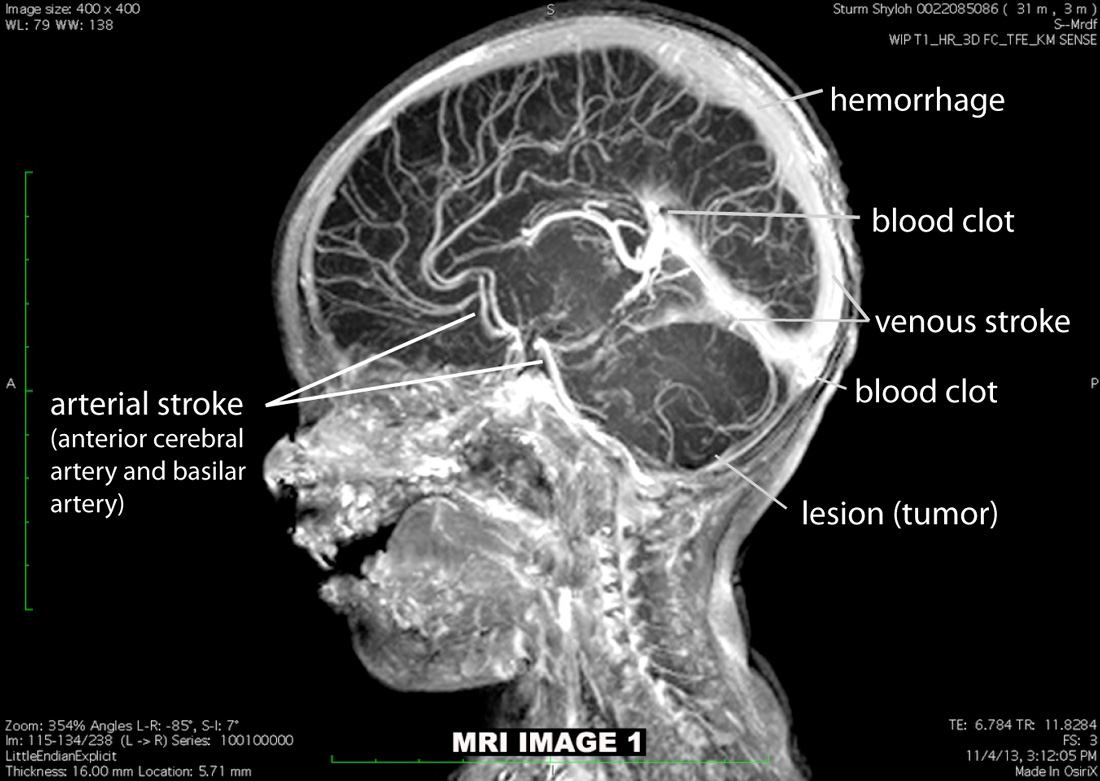

Shyloh has received NO Western medical treatment or pharmaceuticals. Her congenital brain cancer, strokes, brain anoxia (severe loss of oxygen),

right-sided heart failure, epilepsy, and cerebral palsy were treated exclusively with cannabis.

Our daughter, Shyloh Sturm, was born with metastasized brain cancer, cerebral palsy, strokes, and severe epilepsy. According to the medical literature, she could not live longer than three months. While doctors were busily preparing for her death, we treated all four of her “untreatable” conditions ourselves using a special cannabis (marijuana) tea that we made for her when she was two months old. (Shyloh had two German doctor prescriptions for the THC.) In order to treat Shyloh successfully, we had to conduct extensive research—which is how we discovered that heirloom, landrace cannabis sativa plants, combined with hemp flowers, fully treat cerebral palsy, stroke, and epilepsy, and cure even the most aggressive forms of cancer.

Currently, the Apostles’ Oil—a hemp seed oil infused with cannabis flowers—gives us full control over Shyloh’s "untreatable" cerebral palsy and epilepsy. It has helped her recover from multiple arterial and venous strokes and has cured her metastasized brain cancer. Shyloh is now nearly 3 years old, and she is happy and fully functional. In other people, the Apostles' Oil has treated Stage 4 non-small cell metastasized lung cancer, schizophrenia, advanced systemic sarcodisosis, manic-depressive disorder, and many other conditions. With each day, new illnesses are being conquered using the Apostles' Oil.

Shyloh's MRI at 3 months old with cancer, arterial and venous strokes and hemorrhage

(PUT MOUSE OVER IMAGE FOR MORE INFORMATION)